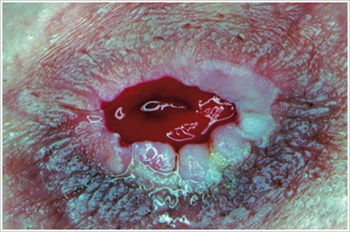

Pioderma gangrenoso

Descrição/Causas:

Uma doença cutânea inflamatória, frequentemente, observada em pacientes com doença intestinal inflamatória (DII), como a doença de Crohn ou colite ulcerativa.

Sintomas:

- Úlceras de formato irregular, vermelhas, dolorosas, infectadas com bordas dobradas vermelhas a violetas; aparecem nas pernas, nas nádegas, no rosto e na área peristomal.